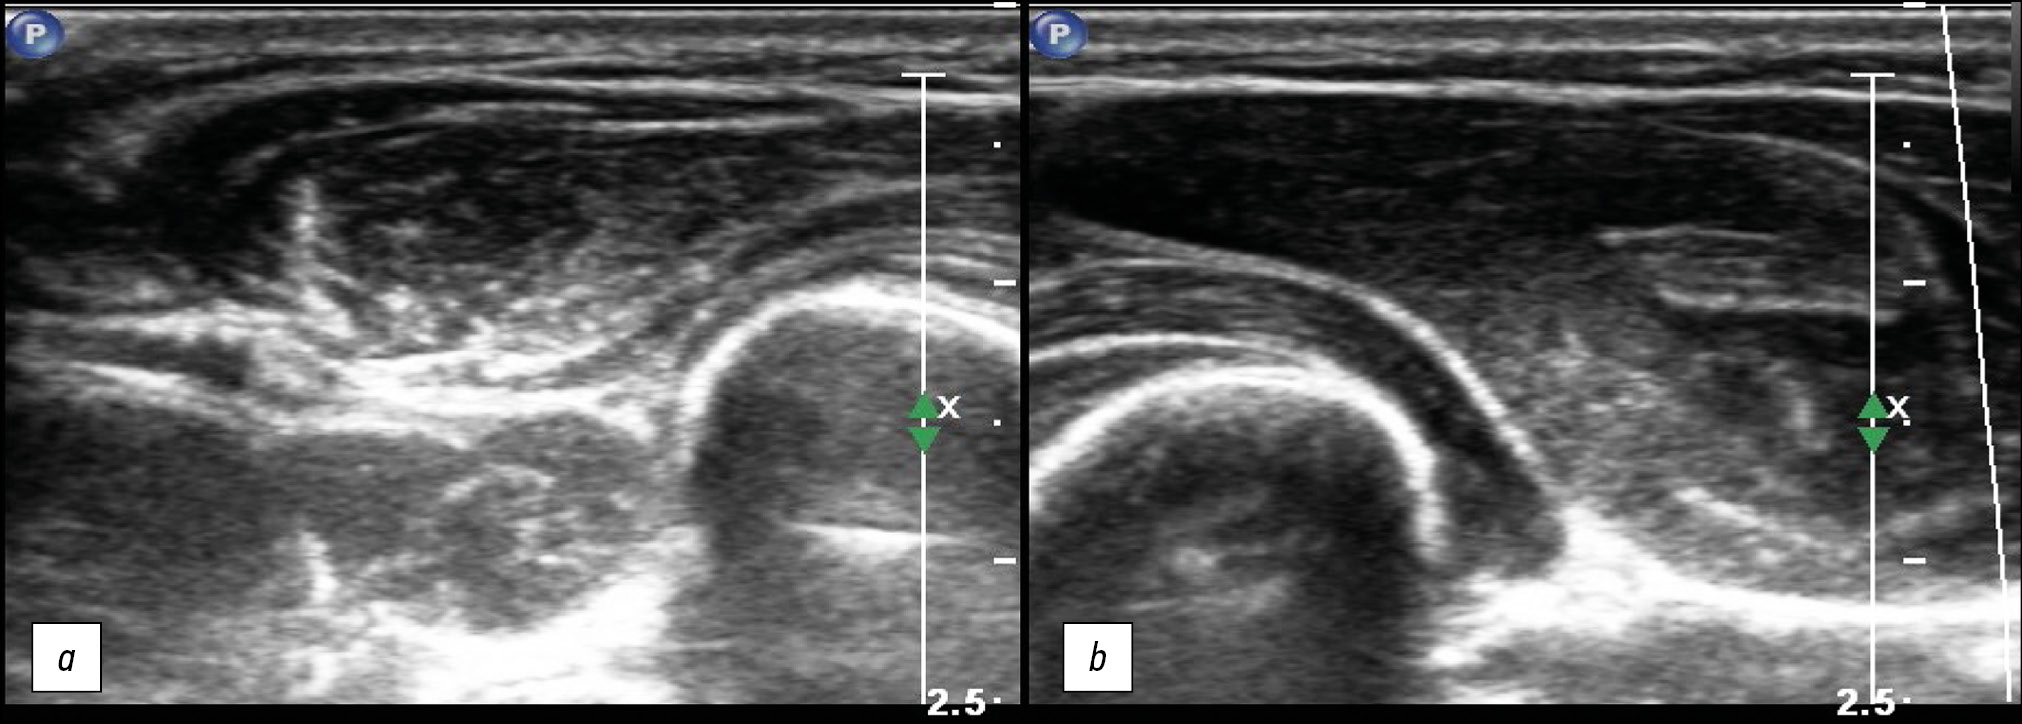

Aseptic necrosis is more common in patients with severe disease, with an incidence of 5% to 58%. Avascular bone necrosis is one of the adverse symptoms of SARS-CoV-2. Avascular necrosis can be detected from 7 days to 2 months from the onset of coronavirus. There was no relationship between the severity of SARS-CoV-2 and the onset of avascular necrosis. The lesion affects all major joints (hip, knee, shoulder, spinal joint, and sacrum), and can be diagnosed by MRI (Fig. 6, 7). Patients treated with corticosteroids for a long time or with higher doses had an increased risk of osteonecrosis [31, 32].

Fig. 6. Magnetic resonance imaging showing aseptic necrosis of the head of the left femur in a patient infected with coronavirus (arrows).

Fig. 7. Aseptic necrosis of the tibial and femoral condyles in a 22-year-old patient infected with coronavirus. Sagittal (a) and axial (b, c) magnetic resonance imaging slices.